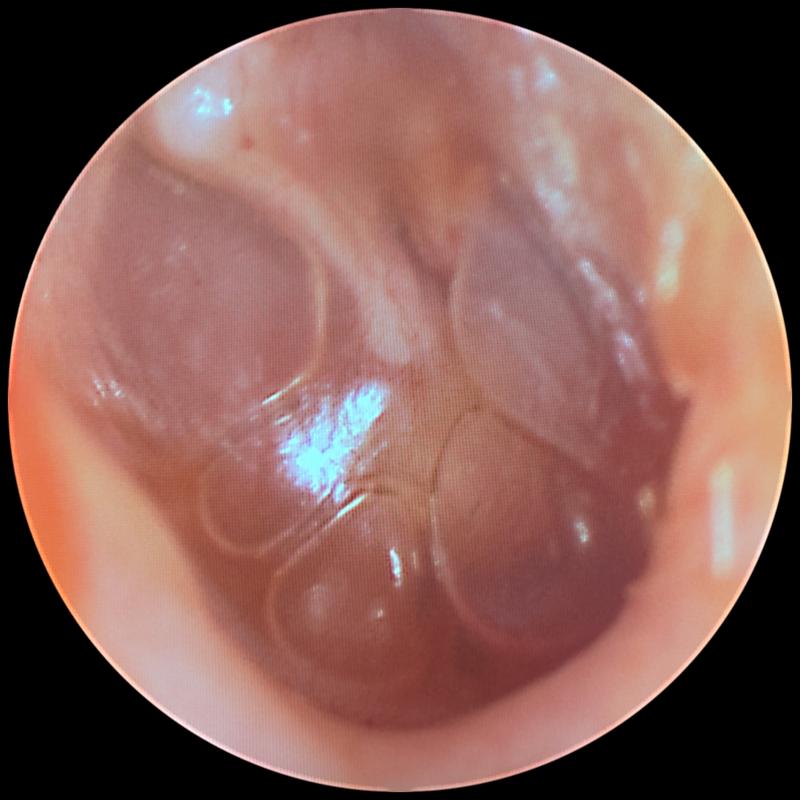

Objawy zapalenia ucha mogą przybierać różne formy, ale najczęściej obserwujemy silny ból, gorączkę oraz ogólne rozdrażnienie. Dzieci, które jeszcze nie potrafią wyrażać swoich myśli słowami, sygnalizują dolegliwości poprzez płacz, pocieranie ucha czy trudności z karmieniem. Zwłaszcza gdy nacisk na ucho przynosi im nieprzyjemne doznania. Czasami maluchy doświadczają również wycieków z ucha. Cóż, maluchy muszą jakoś komunikować swoje potrzeby, a łzy i brudne ubrania znajdują się wśród najczęstszych sposobów! Właściwie złapanie zapalenia ucha przypomina łapanie złotej rybki – każdy rodzic stara się tego unikać, ale kiedy już to się zdarzy, staje przed dylematem: co teraz zrobić?

Wyróżniamy trzy rodzaje zapalenia ucha: zewnętrzne, środkowe i wewnętrzne. To ostatnie wydarza się niezwykle rzadko, natomiast zapalenie ucha środkowego występuje dość często, szczególnie u dzieci. Dlaczego tak się dzieje? Otóż ich trąbki Eustachiusza, czyli te fajne rurki łączące ucho z nosogardłem, są u maluchów krótsze i bardziej poziome. Właśnie dlatego wirusy z kataru mogą z łatwością przedostać się do ucha, co prowadzi do problemów. Pragnę jednak przypomnieć – zapalenie ucha nie przenosi się jak grypa; to wirusy i bakterie mogą być przekazywane. Dlatego dbajmy o zasady higieny, ponieważ to klucz do zdrowia.